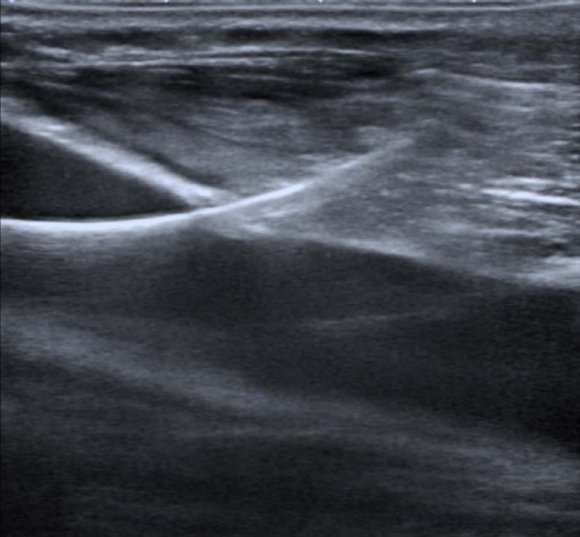

Once the vessel has been channeled, a guide is inserted through the needle, the needle is withdrawn and a catheter is inserted through the guide, after path dilation. Central venous catheterization requires a linear transducer with a 10 MHz frequency or more, ideally narrow band for better maneuverability. Before starting the procedure, it is necessary to have all the requisite supplies, check the status of the catheter, permeabilize it with saline solution and keep in mind the length to be introduced for proper location of its distal end.

The skin must be prepared using an aseptic and antiseptic technique, setting up a sterile field, and the transducer must be covered with a sterile drape. Sterile gel should be used between the transducer cover and the patient's skin, and non-sterile gel between the cover and the transducer, facilitating the transmission of the ultrasound beam. The transducer shall be located according to the anatomical landmarks mentioned below and the vessel insonated in transverse and longitudinal planes. Local anesthetic is injected into soft tissues using ultrasound guidance with two objectives: to avoid intravascular injection and to verify the catheter's access route. Subsequently, the vessel is located in the center of the screen of the equipment obtaining a longitudinal axis, taking into account that catheterization in the longitudinal axis avoids accidental arterial puncture (7,38).

The puncture should be done with a Seldinger needle, with the bevel facing up and ideally at an angle of 45° to the skin. The needle is identified as a linear echogenic structure, which projects an acoustic shadow, and its movement ("ballotment" technique) displaces the adjacent tissues, enabling its location (6). The needle is visualized continuously, entering through the anterior wall of the vessel and aspiration is performed with a syringe attached to it. Obtaining blood confirms its correct location and patency. The insertion of the guide should be visualized in the longitudinal axis of the vessel, demonstrating correct direction (39-41) (Figure 5). The use of the vessel in the axial axis should be considered in cases where the longitudinal axis is not possible, such as in jugular access in patients with a short neck. Progression of the guide, the dilator or the catheter should not put up resistance; if so, the process should not continue, since it may cause vascular dissection. The performance of these steps should be observed under ultrasound guidance (Figure 6). The ultrasound can show the cause of resistance, such as vascular stenosis, vascular thrombosis or insertion towards the opposite wall of the vessel (6). In addition, the trajectory of the guidewire toward distal should be verified and it should not move cephalad.